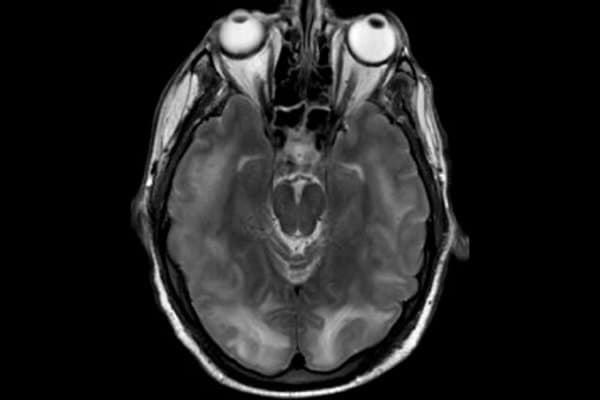

Die zerebrale Bildgebung spielt eine entscheidende Rolle bei der Diagnose des Syndroms. Die MRT ist der CT überlegen, da sie die typischen Veränderungen, wie vasogene Ödeme in der weissen Hirnsubstanz, deutlicher darstellt. Häufig treten die Ödeme bilateral in den Okzipitallappen auf, in Einzelfällen können sie jedoch auch einseitig oder in der grauen Hirnsubstanz auftreten. Es besteht auch die seltene Möglichkeit einer transtentoriellen Einklemmung aufgrund des Verdrängungseffekts.